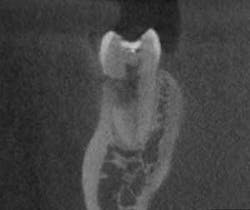

- This is another case of what could easily be misdiagnosed as internal resorption on tooth #No. 24. If you look closely in Figure 7, the outline of the canal can be seen.

- In Figure 8, the lesion is advanced significantly (one-and-a-half years had gone by) the irregular borders and moth-eaten appearance is easily observed.

- Definitive diagnosis: external resorption.